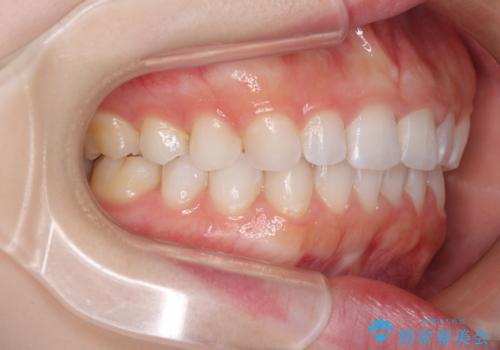

デコボコと深い咬み合わせの改善 インビザラインによる矯正治療

- 口元のデコボコと深い咬み合わせ(ディープバイト)を気にして来院された患者様です。

インビザラインによる上下歯列の拡大と、IPR(歯と歯の間を削る)にるスペースの獲得により、口元のデコボコとディープバイトを改善することとしました。

インビザラインは、装着していない時間がどれだけ短いかが、治療期間を大きく左右します。こちらの患者様は1日22時間以上、毎日欠かさず装着してくださったため、1年強という短期間で満足のいく歯列に整えることができました。